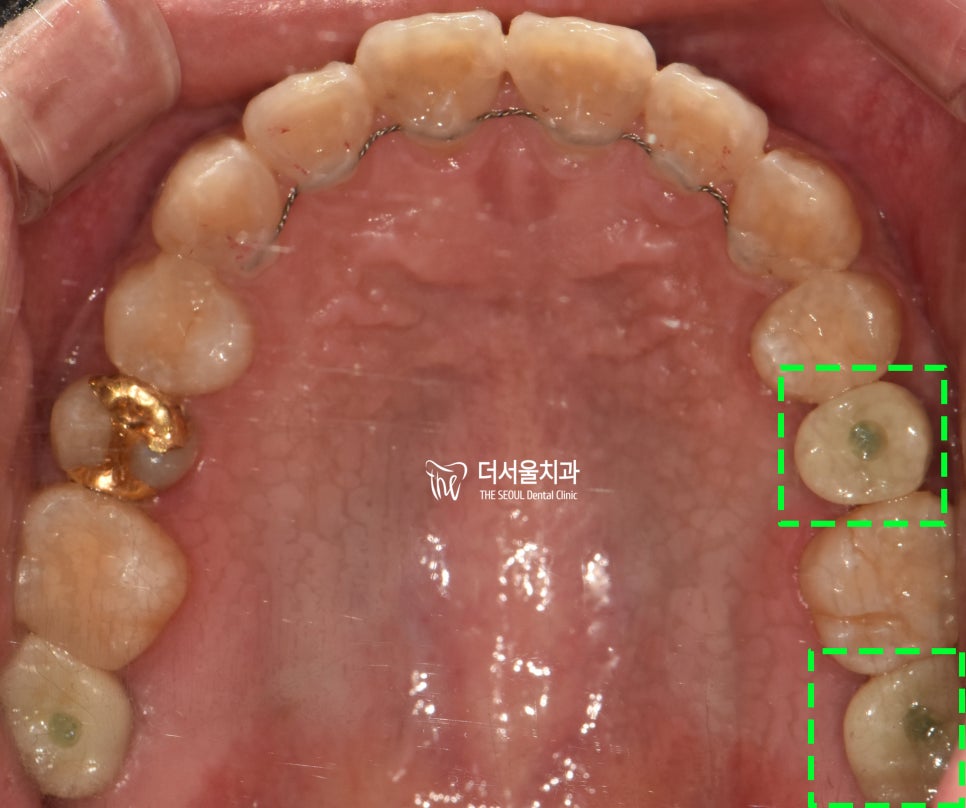

그리고 교합면을 보면,

25, 27번 자리에

최종 보철이 세팅된 것을 볼 수 있습니다.

깔끔히 잘 마무리 되었네요.